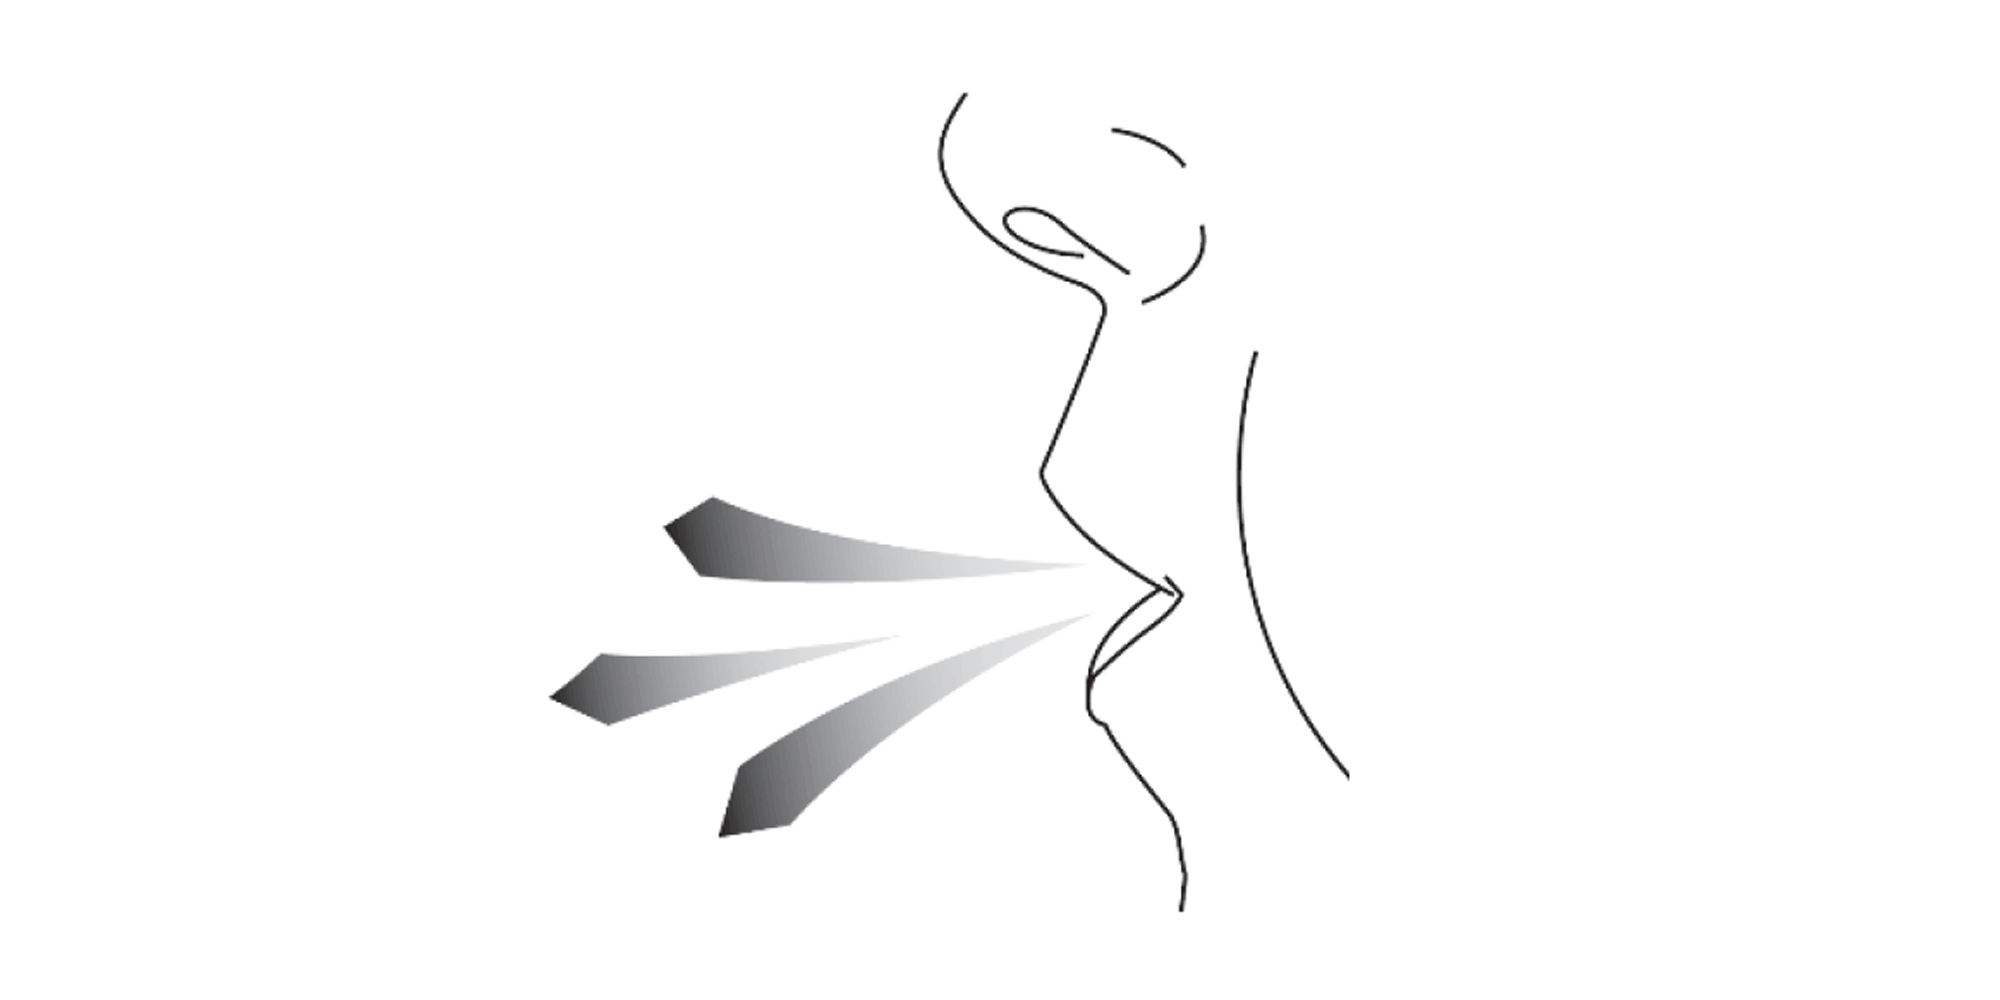

Hold the Vertical-Haler away from your mouth and breathe out completely. Do not breathe into the Vertical-Haler at any time.

Keep your head in an upright position and close your lips tightly around the mouthpiece. Breathe in slowly and deeply until your lungs are full (it’s normal to hear a vibrating sound when breathing in). Take the Vertical-Haler out of your mouth and hold your breath for as long as is comfortable. Then breathe normally.